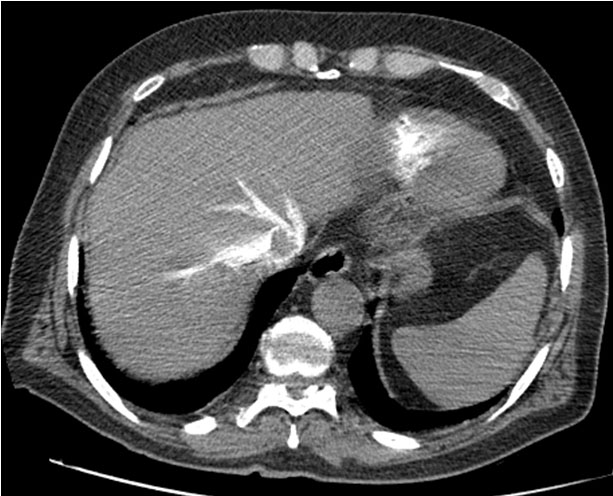

The chest X-ray showed mild cardiomegaly and a concave left middle arch. Computed tomography (CT) angiography image through the level of pulmonary trunk in the arterial phase showed the presence of low-dense occlusive intra-arterial material in the proximal pulmonary arteries bilaterally (Figure 1) and a reflux of contrast material into the inferior vena cava (IVC) and hepatic veins (Figure 2). For treatment, the patient benefitted from thrombolysis in emergency and was put on anticoagulants for up to six months with a good evolution under treatment.

Figure 2: Axial CT angiography image through the level of the liver in the arterial phase shows the reflux of contrast material into the IVC and hepatic veins.

Chest CT angiography and ventilation perfusion scan has established itself as the gold standard in the diagnosis of PE. Several prospective studies have shown the safety of excluding PE on the basis of negative CT angiography, in patients with a low clinical probability but positive D-dimers, and in patients with a high clinical probability. The typical finding of PE on CT pulmonary angiography is filling defects within the pulmonary arterial system. When the artery is viewed in its axial plane, the central filling defect of a non-occlusive thrombus is surrounded by a thin rim of contrast, which is called Polo Mint sign, or an adjacent thin stream of contrast. The embolus makes an acute angle with the vessel. The affected vessel may also enlarge. Acute pulmonary thromboemboli on non-contrast chest CT may appear as intraluminal hyper densities. Indirect signs of the severity of PE on CT chest angiography include signs of right heart strain such as increased right ventricle (RV)/left ventricular (LV) ratio (>1 in axial plane, >0.9 in 4-chamber reconstruction), flattening and ventricular septum inversion, and reflux of contrast material into the IVC and hepatic veins. Dual-energy CT holds much promise for the diagnosis and prognosis of PE [13],[14].